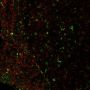

This antibody recognizes a glycoprotein of 110 kDa, which is identified as CD68. It is important for identifying macrophages in tissue sections. It stains macrophages in a wide variety of human tissues, including Kupffer cells and macrophages in the red pulp of the spleen, in lamina propria of the gut, in lung alveoli, and in bone marrow. It reacts with myeloid precursors and peripheral blood granulocytes. It also reacts with plasmacytoid T cells, which are supposed to be of monocyte/macrophage origin. It shows strong granular cytoplasmic staining of chronic and acute myeloid leukemia and also reacts with rare cases of true histiocytic neoplasia. Lymphomas are negative or show few granules.

IF (verified), IHC, FFPE (verified)

IF (verified)|IHC (FFPE) (verified)

Higher concentration may be required for direct detection using primary antibody conjugates than for indirect detection with secondary antibody|Immunofluorescence (direct conjugate): 1-5 ug/mL|Immunohistology (formalin) 2-4 ug/mL|Staining of formalin-fixed tissues is enhanced by boiling tissue sections in 10 mM citrate buffer, pH 6.0, for 10-20 min followed by cooling at RT for 20 minutes|Flow Cytometry 0.5-1 ug/million cells/0.1 mL|Optimal dilution for a specific application should be determined by user